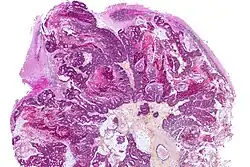

A brain metastasis is a cancer that has metastasized (spread) to the brain from another location in the body and is therefore considered a secondary brain tumor.[1][2] The metastasis typically shares a cancer cell type with the original site of the cancer.[3] Metastasis is the most common cause of brain cancer, as primary tumors that originate in the brain are less common.[4] The most common sites of primary cancer which metastasize to the brain are lung, breast, colon, kidney, and skin cancer. Brain metastases can occur in patients months or even years after their original cancer is treated. Brain metastases have a poor prognosis for cure, but modern treatments are allowing patients to live months and sometimes years after the diagnosis.[5]

Diagnosis

Brain imaging (neuroimaging such as CT or MRI) is needed to determine the presence of brain metastases.[6] In particular, contrast-enhanced MRI is the best method of diagnosing brain metastases, though detection is primarily done by CT.[10] Biopsy is often recommended to confirm diagnosis.[6]